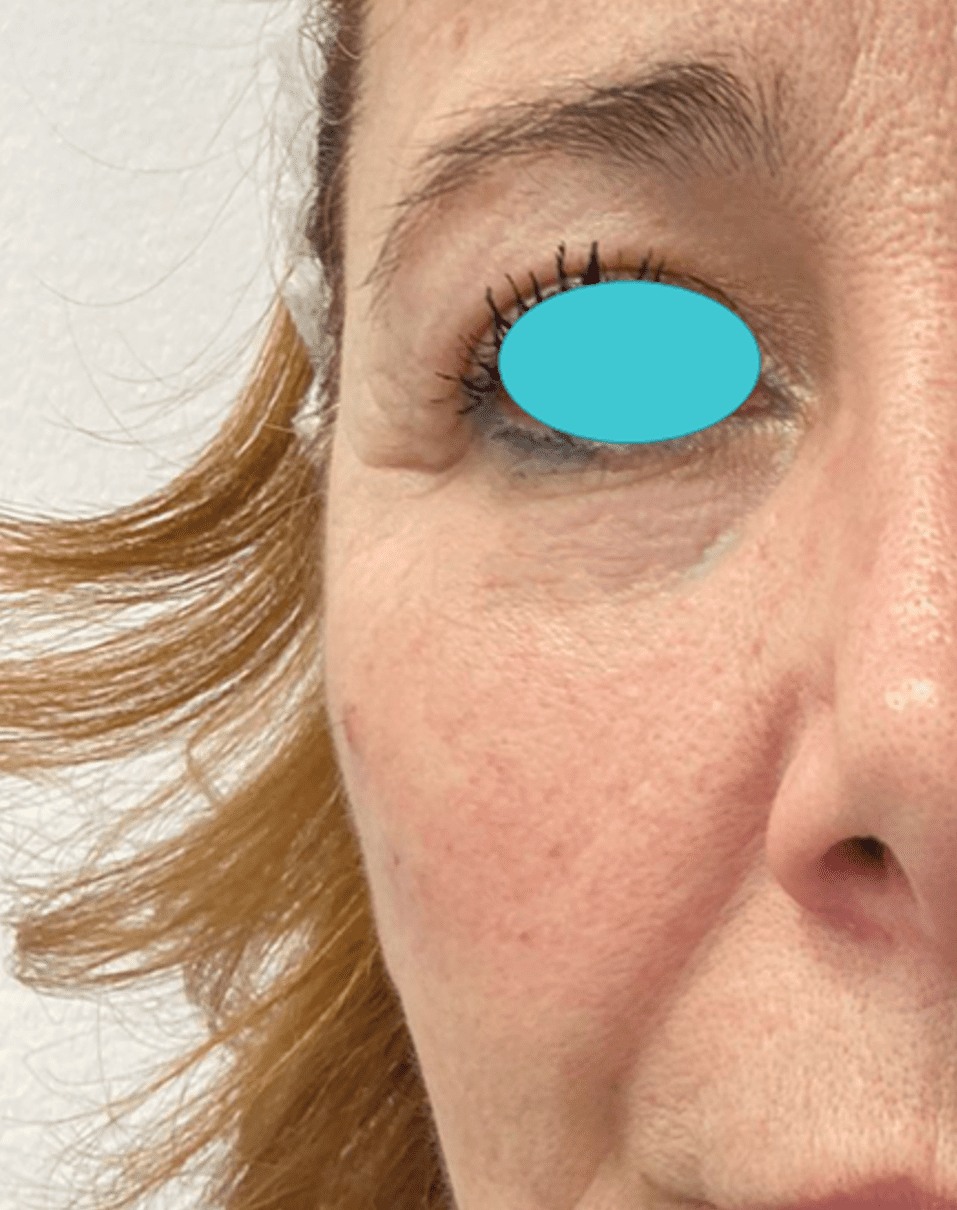

Eye Bag, Dark Circles & Tear Trough

Before

After